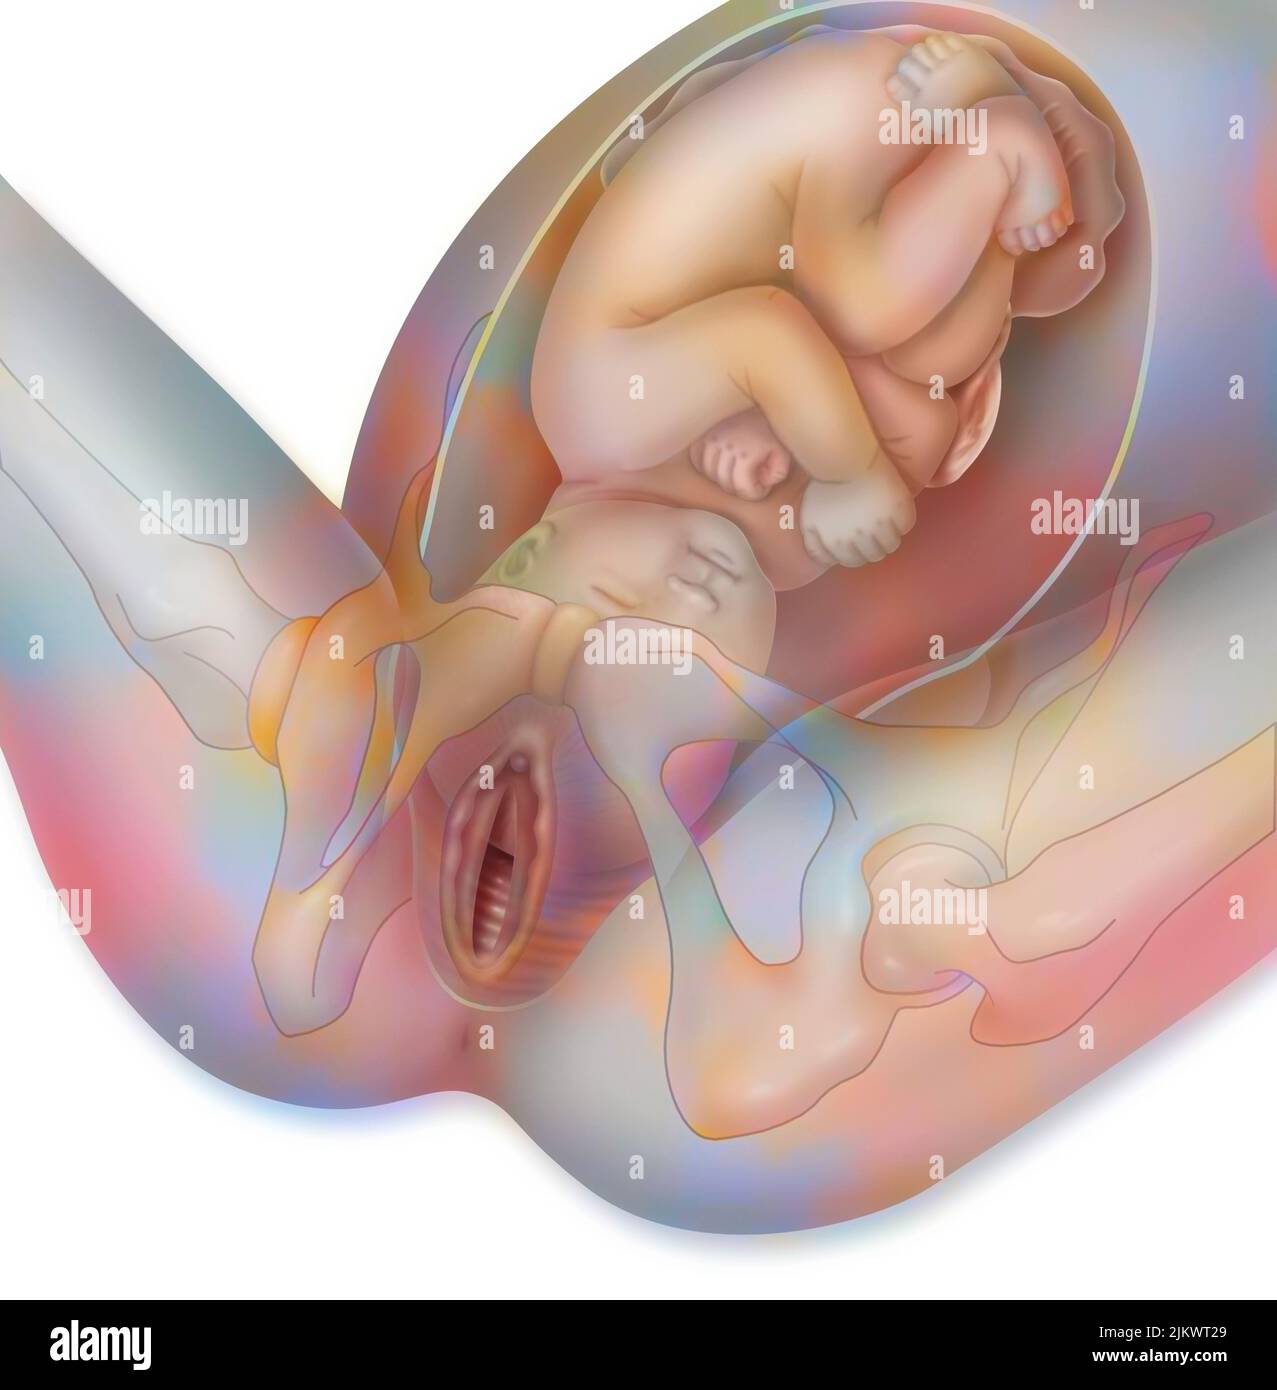

Fetus Positions in Uterus, Illustration Stock Photohttps://www.alamy.com/image-license-details/?v=1https://www.alamy.com/fetus-positions-in-uterus-illustration-image353173031.html

Fetus Positions in Uterus, Illustration Stock Photohttps://www.alamy.com/image-license-details/?v=1https://www.alamy.com/fetus-positions-in-uterus-illustration-image353173031.htmlRF2BEGBPF–Fetus Positions in Uterus, Illustration

Childbirth, stage 1: the baby is engaged in the pelvis. Stock Photohttps://www.alamy.com/image-license-details/?v=1https://www.alamy.com/childbirth-stage-1-the-baby-is-engaged-in-the-pelvis-image476926081.html

Childbirth, stage 1: the baby is engaged in the pelvis. Stock Photohttps://www.alamy.com/image-license-details/?v=1https://www.alamy.com/childbirth-stage-1-the-baby-is-engaged-in-the-pelvis-image476926081.htmlRF2JKWT29–Childbirth, stage 1: the baby is engaged in the pelvis.